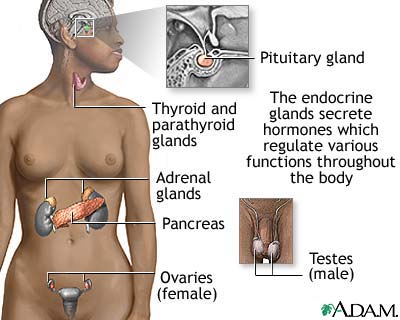

Papillary carcinoma of the thyroid is the most common cancer of the thyroid gland. The thyroid gland is located in front of the lower neck.